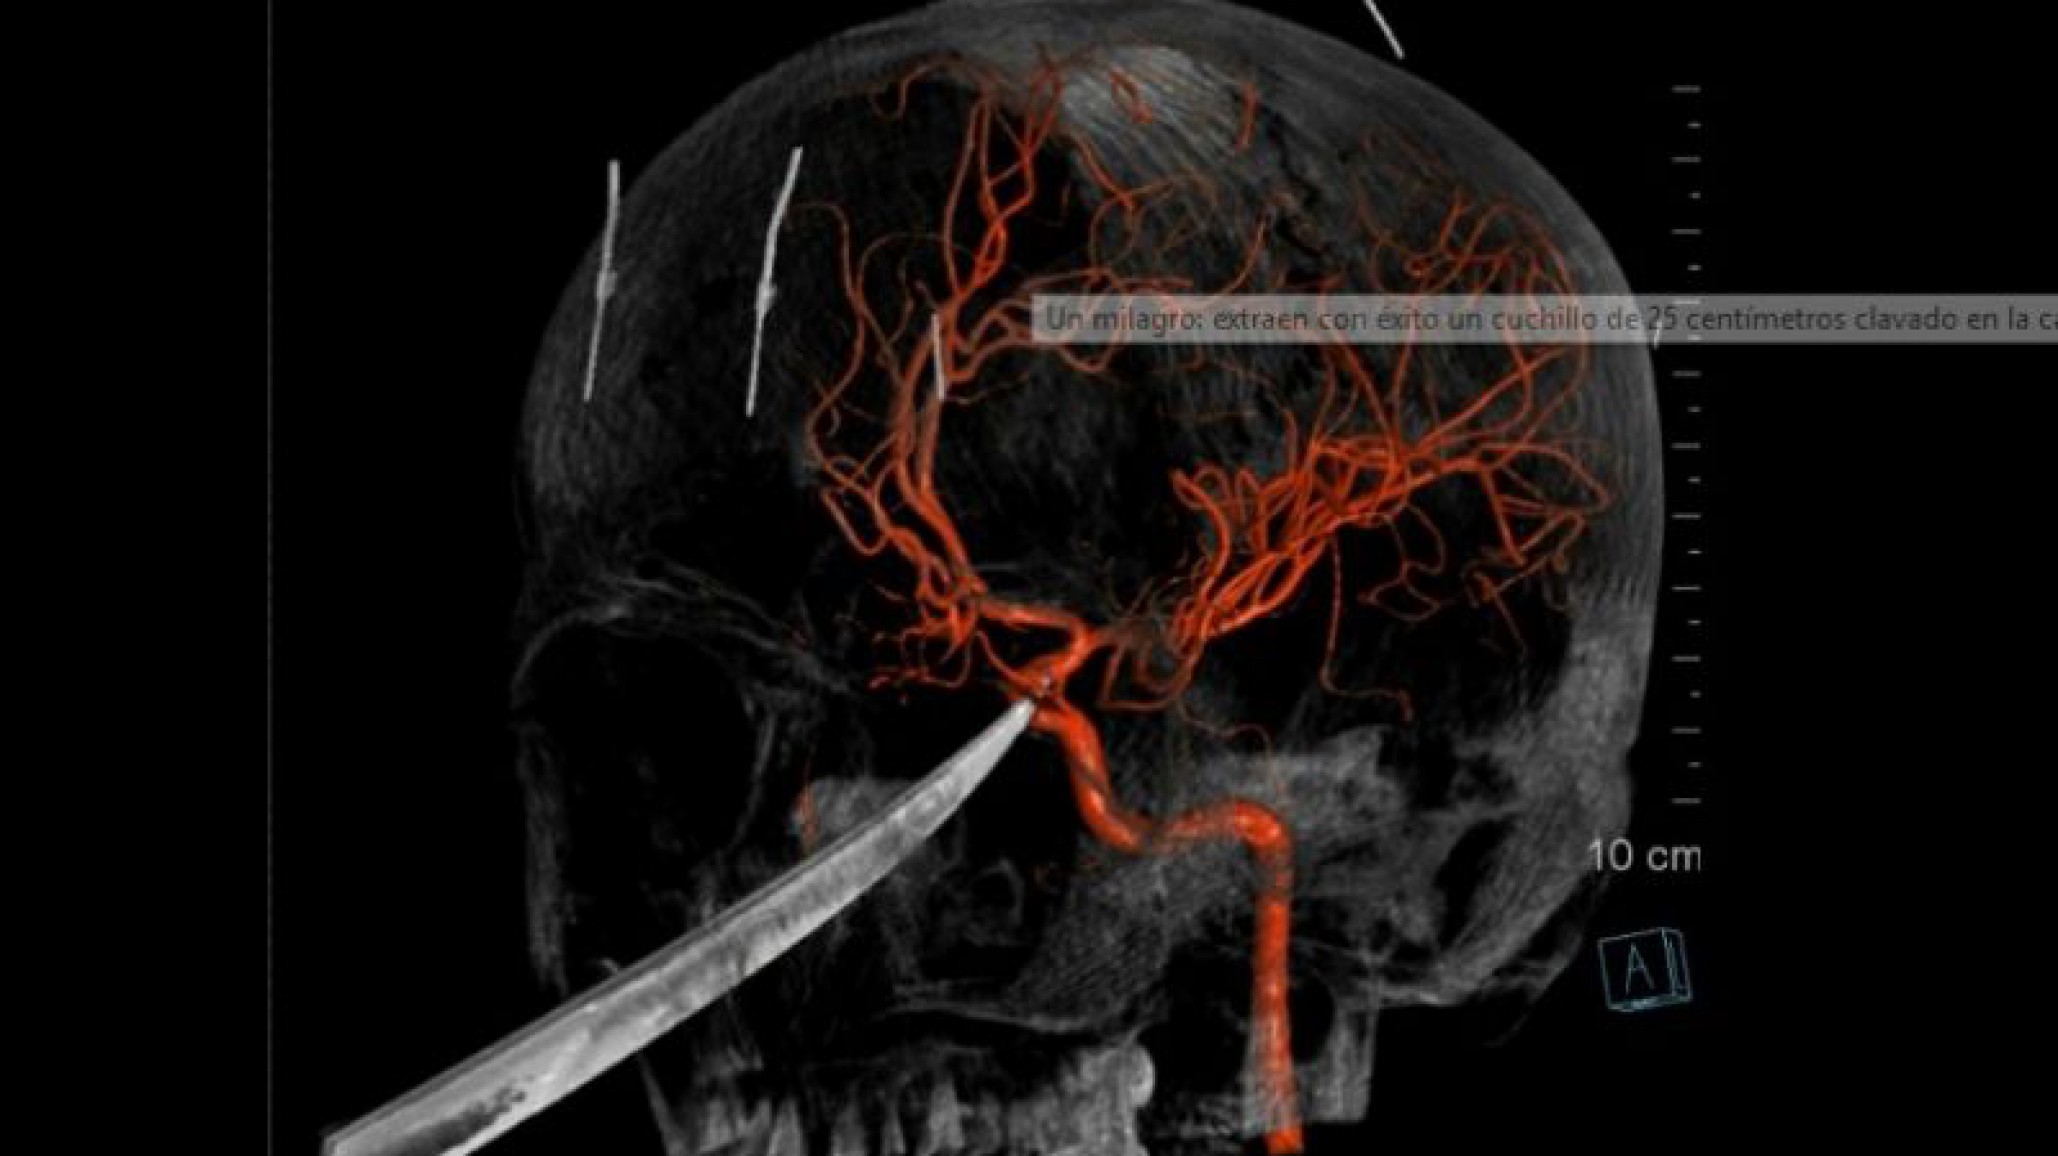

Extrajeron un cuchillo de 25 centímetros del cráneo de un adolescente

El cirujano Koji Ebersole, realizó la cirugía, el experto explicó que la herida del cráneo era muy grave, los rayos X mostraban la profundidad del cuchillo clavado en su cráneo que se encontraba debajo de su cerebro y presionando la arteria carótida. El procedimiento fue exitoso publicó RM.